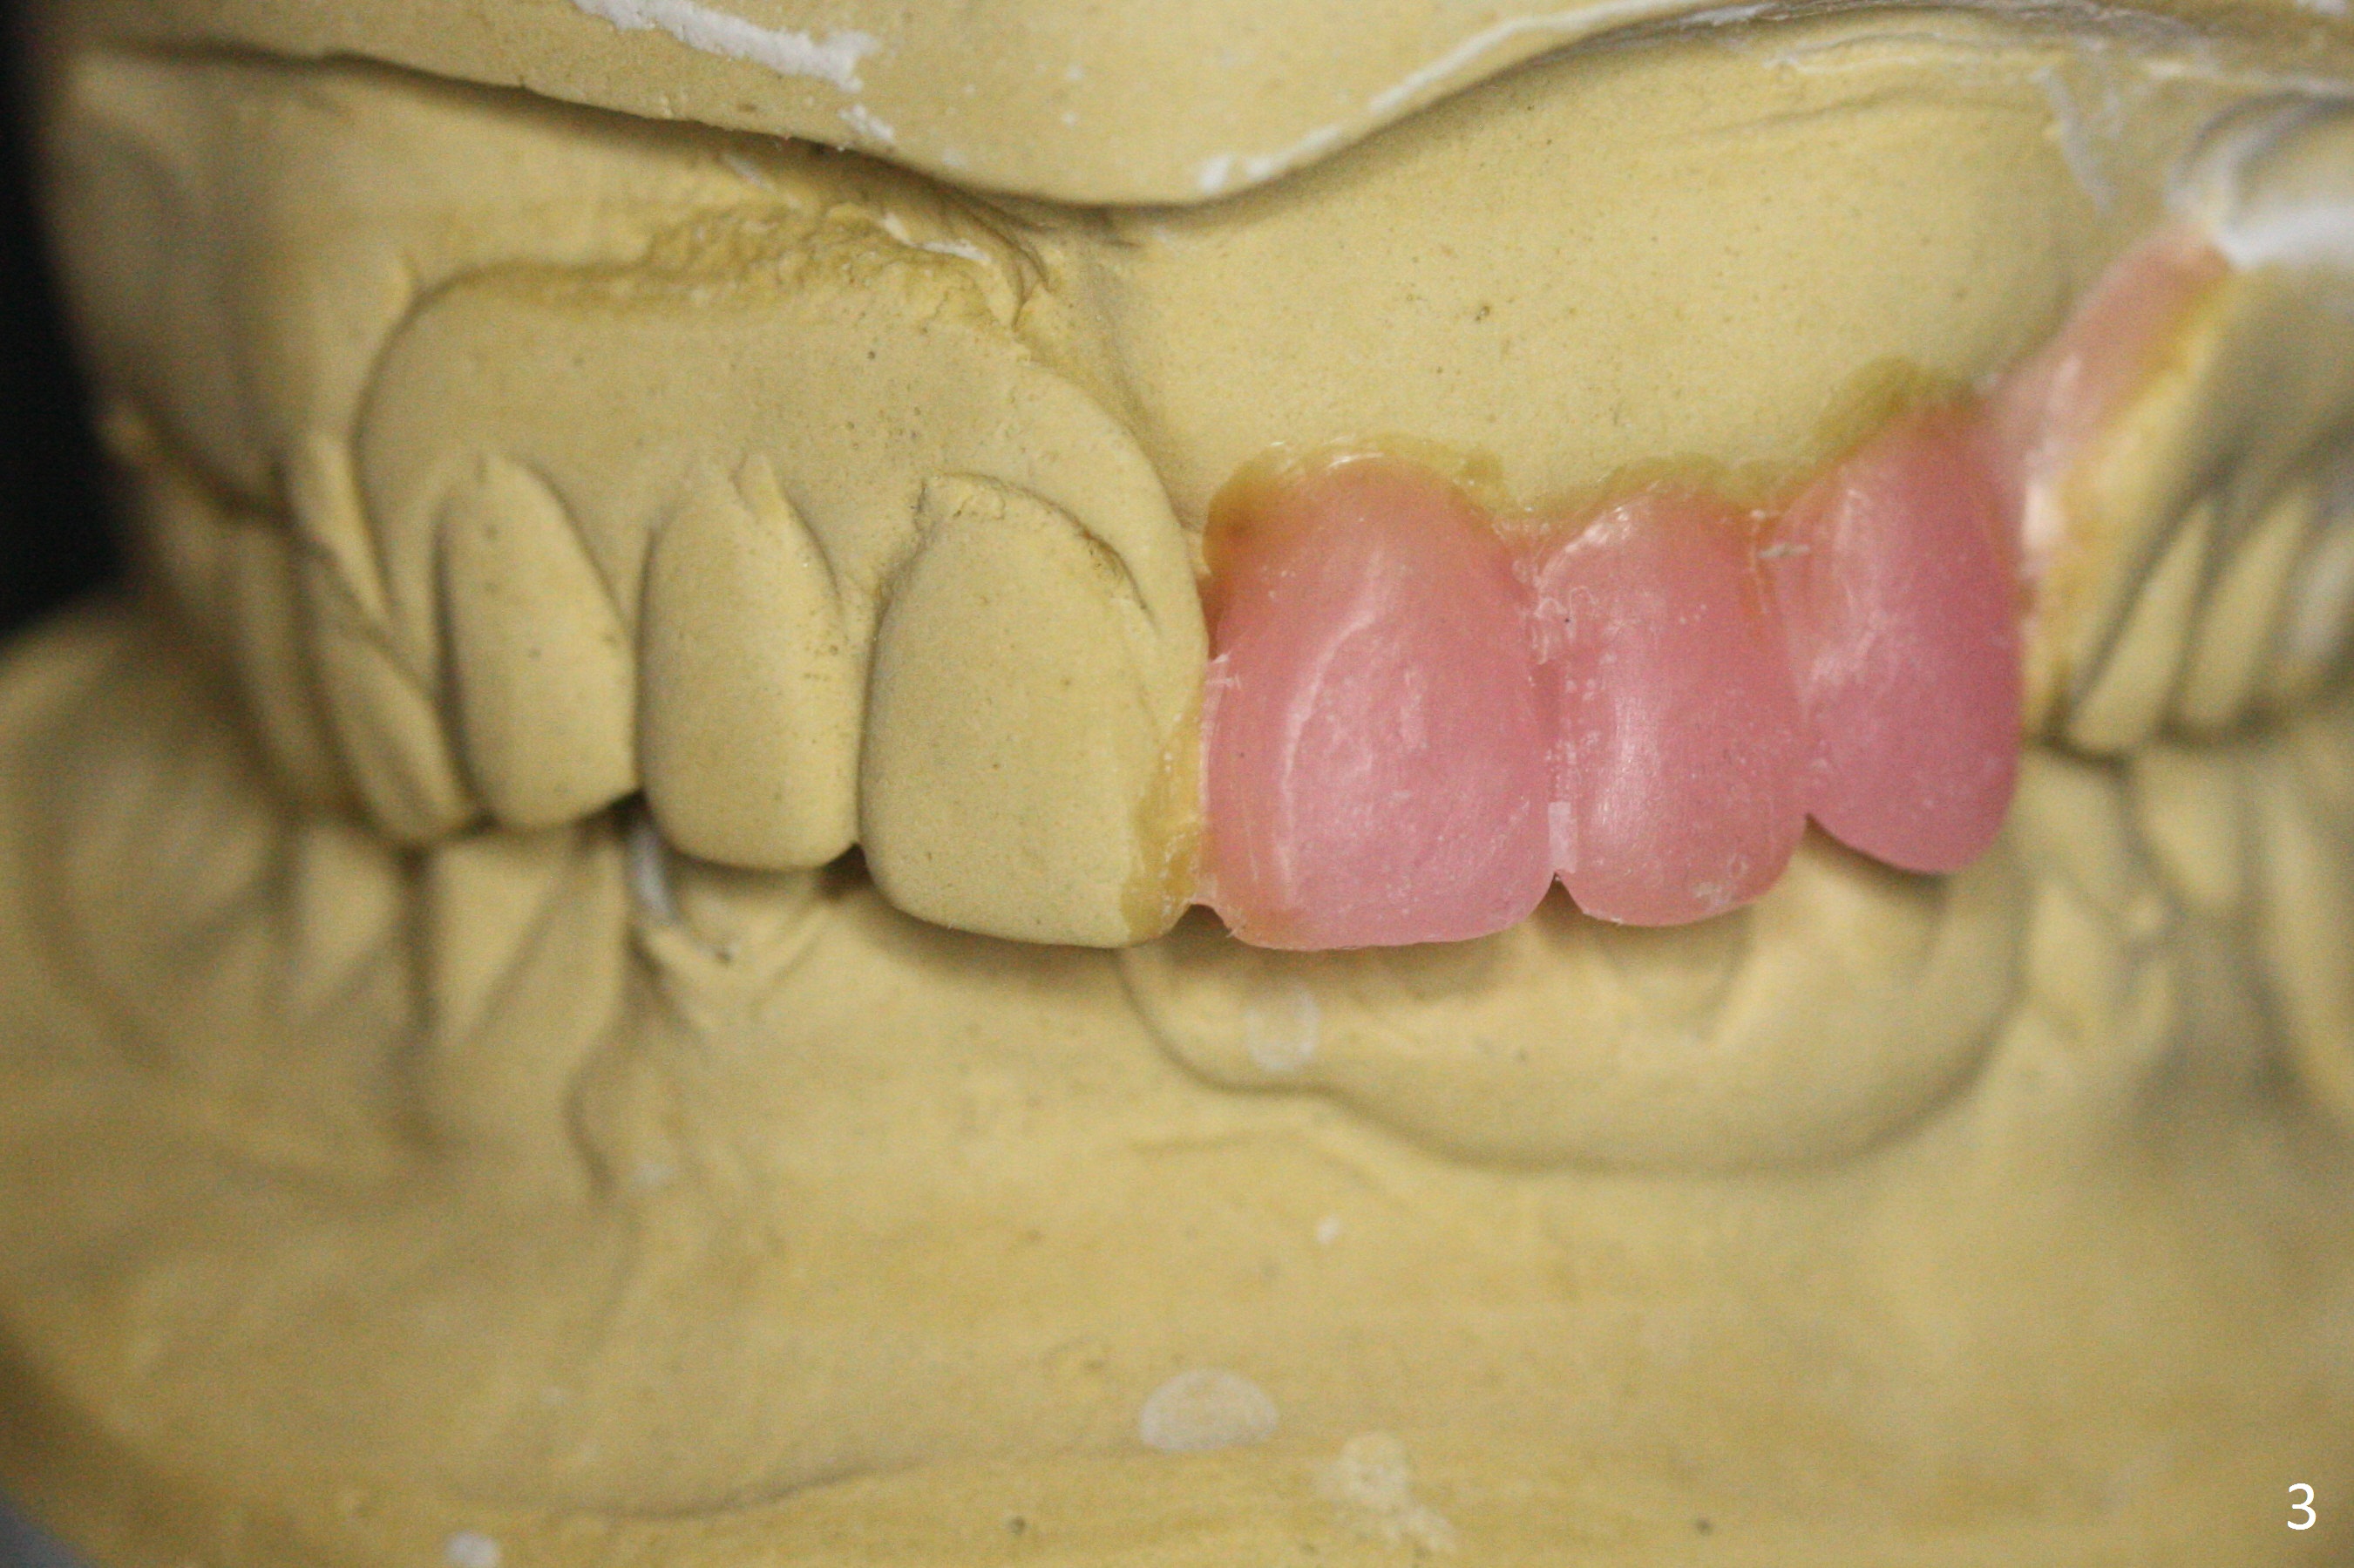

A 62-year-old woman has poor dentition (Fig.1). The most critical area is the upper left anterior: #9-11, which were extracted 4 months earlier (Fig.2). Implants will be placed at #9 and 11 with fabrication of a provisional bridge (Fig.3). After incision, use Magic Split to start bone expansion, followed by micro-osteotomes 1 and 1.5 mm and Magic Osteotomes 3 and 3.8 mm. If the transition between 1.5 and 3 mm osteotomes is not smooth, apply RT2. Place the smallest bone-level implants (for hybrid denture in the future) with gold coated abutments. There should be no interference with or without the partials and in and out. Next step should be removing splinted crowns at #26 and 27 (Fig.1), RCT for #27 and immediate implant at #26 (Fig.5,6 Metronidazole). In fact the splinted crowns at #26 and 27 were lost last week. The patient thinks that she needs 2 implants. The next one is to remove the crown at #5 for RCT (Fig.4).